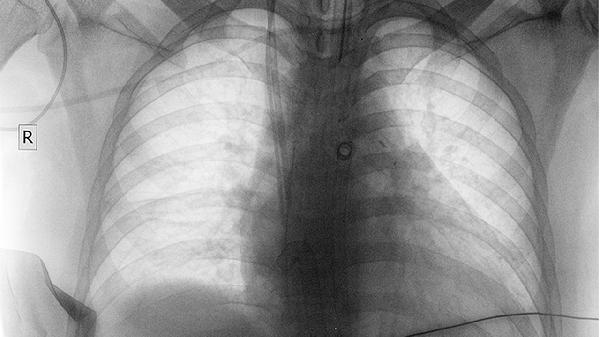

肺结节4mm稍高密度影怎么回事,怎么办

肺结节4mm稍高密度影可能与炎症、结核、良性肿瘤等因素有关,可通过定期复查、药物治疗、手术切除等方式干预。肺部出现4毫米稍高密度影通常属于微小肺结节,多数为良性病变,但需结合临床特征综合评估。